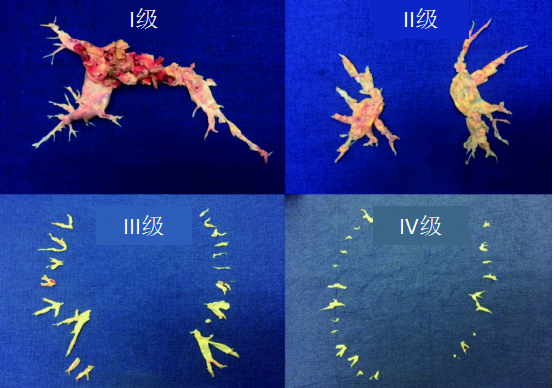

根据血栓的位置,UCSD建议将CTEPH中的肺血栓栓塞分为各级:Ⅰ级:累及肺动脉主干;Ⅱ级:始于肺动脉段;Ⅲ级:始于肺动脉亚段;Ⅳ级:仅限于肺动脉亚段。此外,IC级为单只肺动脉完全闭塞,右肺动脉或左肺动脉完全闭塞,0级则未见相应肺内CTEPH(图 5)。值得注意的是,这种分类是在PEA术中进行的分类。随着成像方式的改进,术前预测疾病水平的能力有所提高,尽管不是所有情况都能进行预测。对于Ⅲ至Ⅳ级病变即使专业性更强的术者进行手术,并发症的发生率也更高,但手术成功后血流动力学仍有望得到改善。